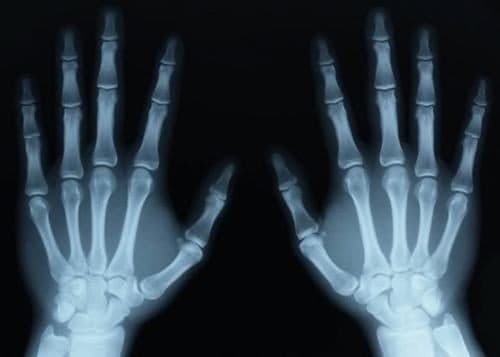

Thăm khám tại cơ sở y tế, bác sĩ sẽ hỏi về triệu chứng trật khớp và nguyên nhân tai nạn đồng thời kiểm tra các ngón tay lân cận xem có bị ảnh hưởng không. Người bệnh được chỉ định chụp X quang để đánh giá mức độ tổn thương.